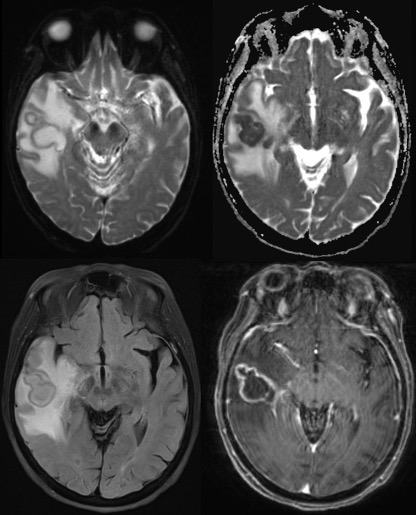

Here, given the immunosuppressed state and the clinical suspicion for infection, the patient’s immunosuppressive medications were paused. Pre-operative MRI (see Fig 1). showed a 3.7 x 2.3 x 2.3 cm right temporal lesion with surrounding edema, regional mass effect with local sulcal effacement. Trace DW images showed a hyperintensity with low ADC indicating restricted diffusion, consistent with an abscess.

Figure 1. DWI, ADC, FLAIR and T1-post gadolinium MRI prior to the surgery showing right temporal lesion.